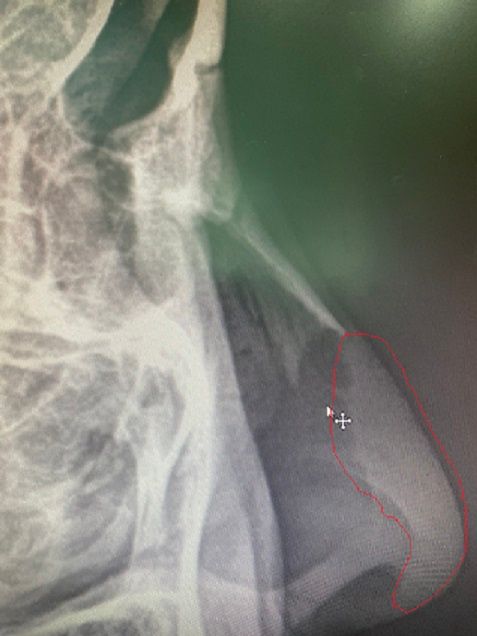

몇 일 전에 찍은 코 엑스레이 사진인데요.

사진에 제가 빨갛게 표시해놓은 부분요.

이 부분은 뼈도 아닐텐데, 엑스레이에서 왜 하얗게 보이는 건가요?

코 엑스레이에 대해 궁금하시군요. 붉은색으로 표시하신 부분은 코에 존재하는 연골입니다. 뼈보다는 덜 하얗게 보이지만 분명 그 윤곽을 확인할 수 있습니다.

해당부분은 연골로 칼슘등이 있고 이또한 고체성분이기 때문에 뼈보다는 옅은 흰색으로 보일 수 있습니다